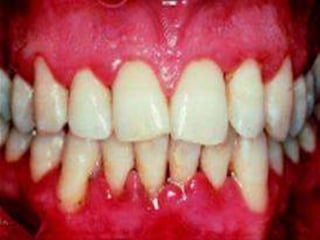

Various differential diagnosis for desquamative gingivitis

are:



lichen planus

bullous pemphigoid

mucous membrane pemphigoid

pemphigus vulgaris

EM

0.05% FLUOCINONIDE OINTMENT for erosive ,bullous or

ulcerative type of LP .

Gingival tray with 0.05% clobetasol propionate along with

1lakh I.U/ML of nystatin in orabase.

Intra lesional injections of triamcinolone acetonide (1020mg) or short term regime of 40 mg prednisolone for 5

days followed by 10-20mg for additional 2 weeks in case

of severe cases